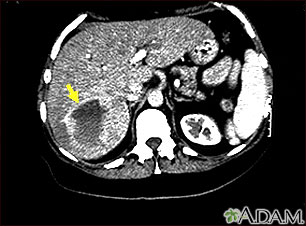

Esta TC abdominal superior muestra un tumor de un vaso sanguíneo (hemangioma) en el hígado.